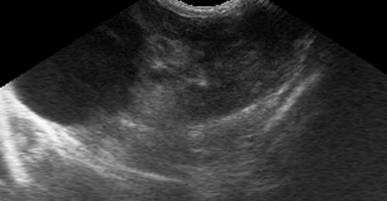

Кисти нирок

Прості кисти нирок, як правило, є

випадковими знахідками. Вони виявляються при ультразвуковому обстеженні як

поодинокі, круглі, ехонегативні утворення з дистальним підсиленням, що

викликане підвищеною звуковою трансмісією. Складні кисти можуть мати ехогенні

перетинки або уламки.

Рис. 2. Проста киста правої нирки

(стрілка) у кота 2 років